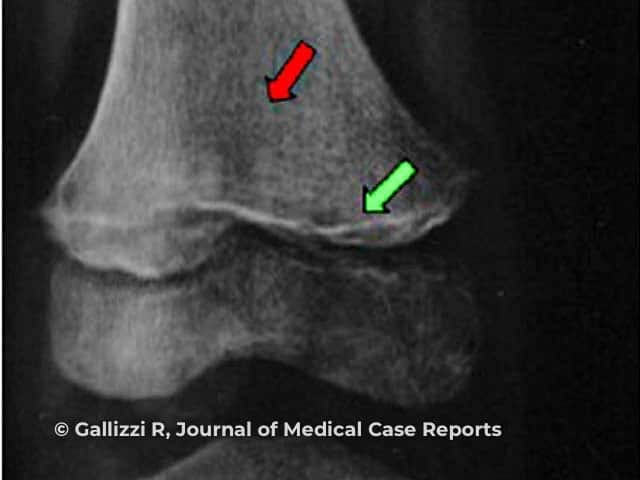

In children, characteristic changes are seen on X-ray:

Frankel sign (green arrow), Trummerfeld zone (red arrow)

Image from: Gallizzi R, Valenzise M, Passanisi S, Pajno GB, De Luca F, Zirilli G. Scurvy may occur even in children with no underlying risk factors: a case report. J Med Case Rep. 2020;14(1):18.